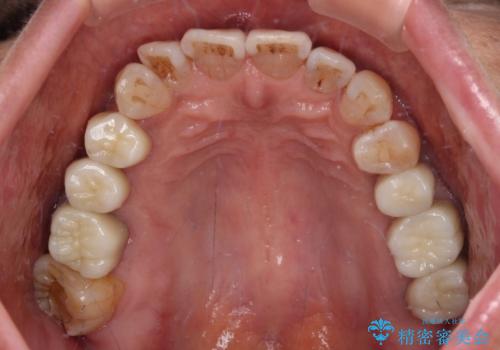

治療を終えたばかりですが、出血を改善するためには作り直しが必要と判断し、オールセラミッククラウンにて補綴治療することとしました。

他にも、咬合時に痛みを感じる歯や、欠損により咬みにくい奥歯などをインプラントを用いて治療を行うこととしました。

仮歯に置き換えた時点で歯肉からの出血は収まり、不快感が改善されました。

右下は、残存歯の状態があまり良くなかったため、今後抜歯となったことを想定して、最後臼歯のインプラントを決定しました。